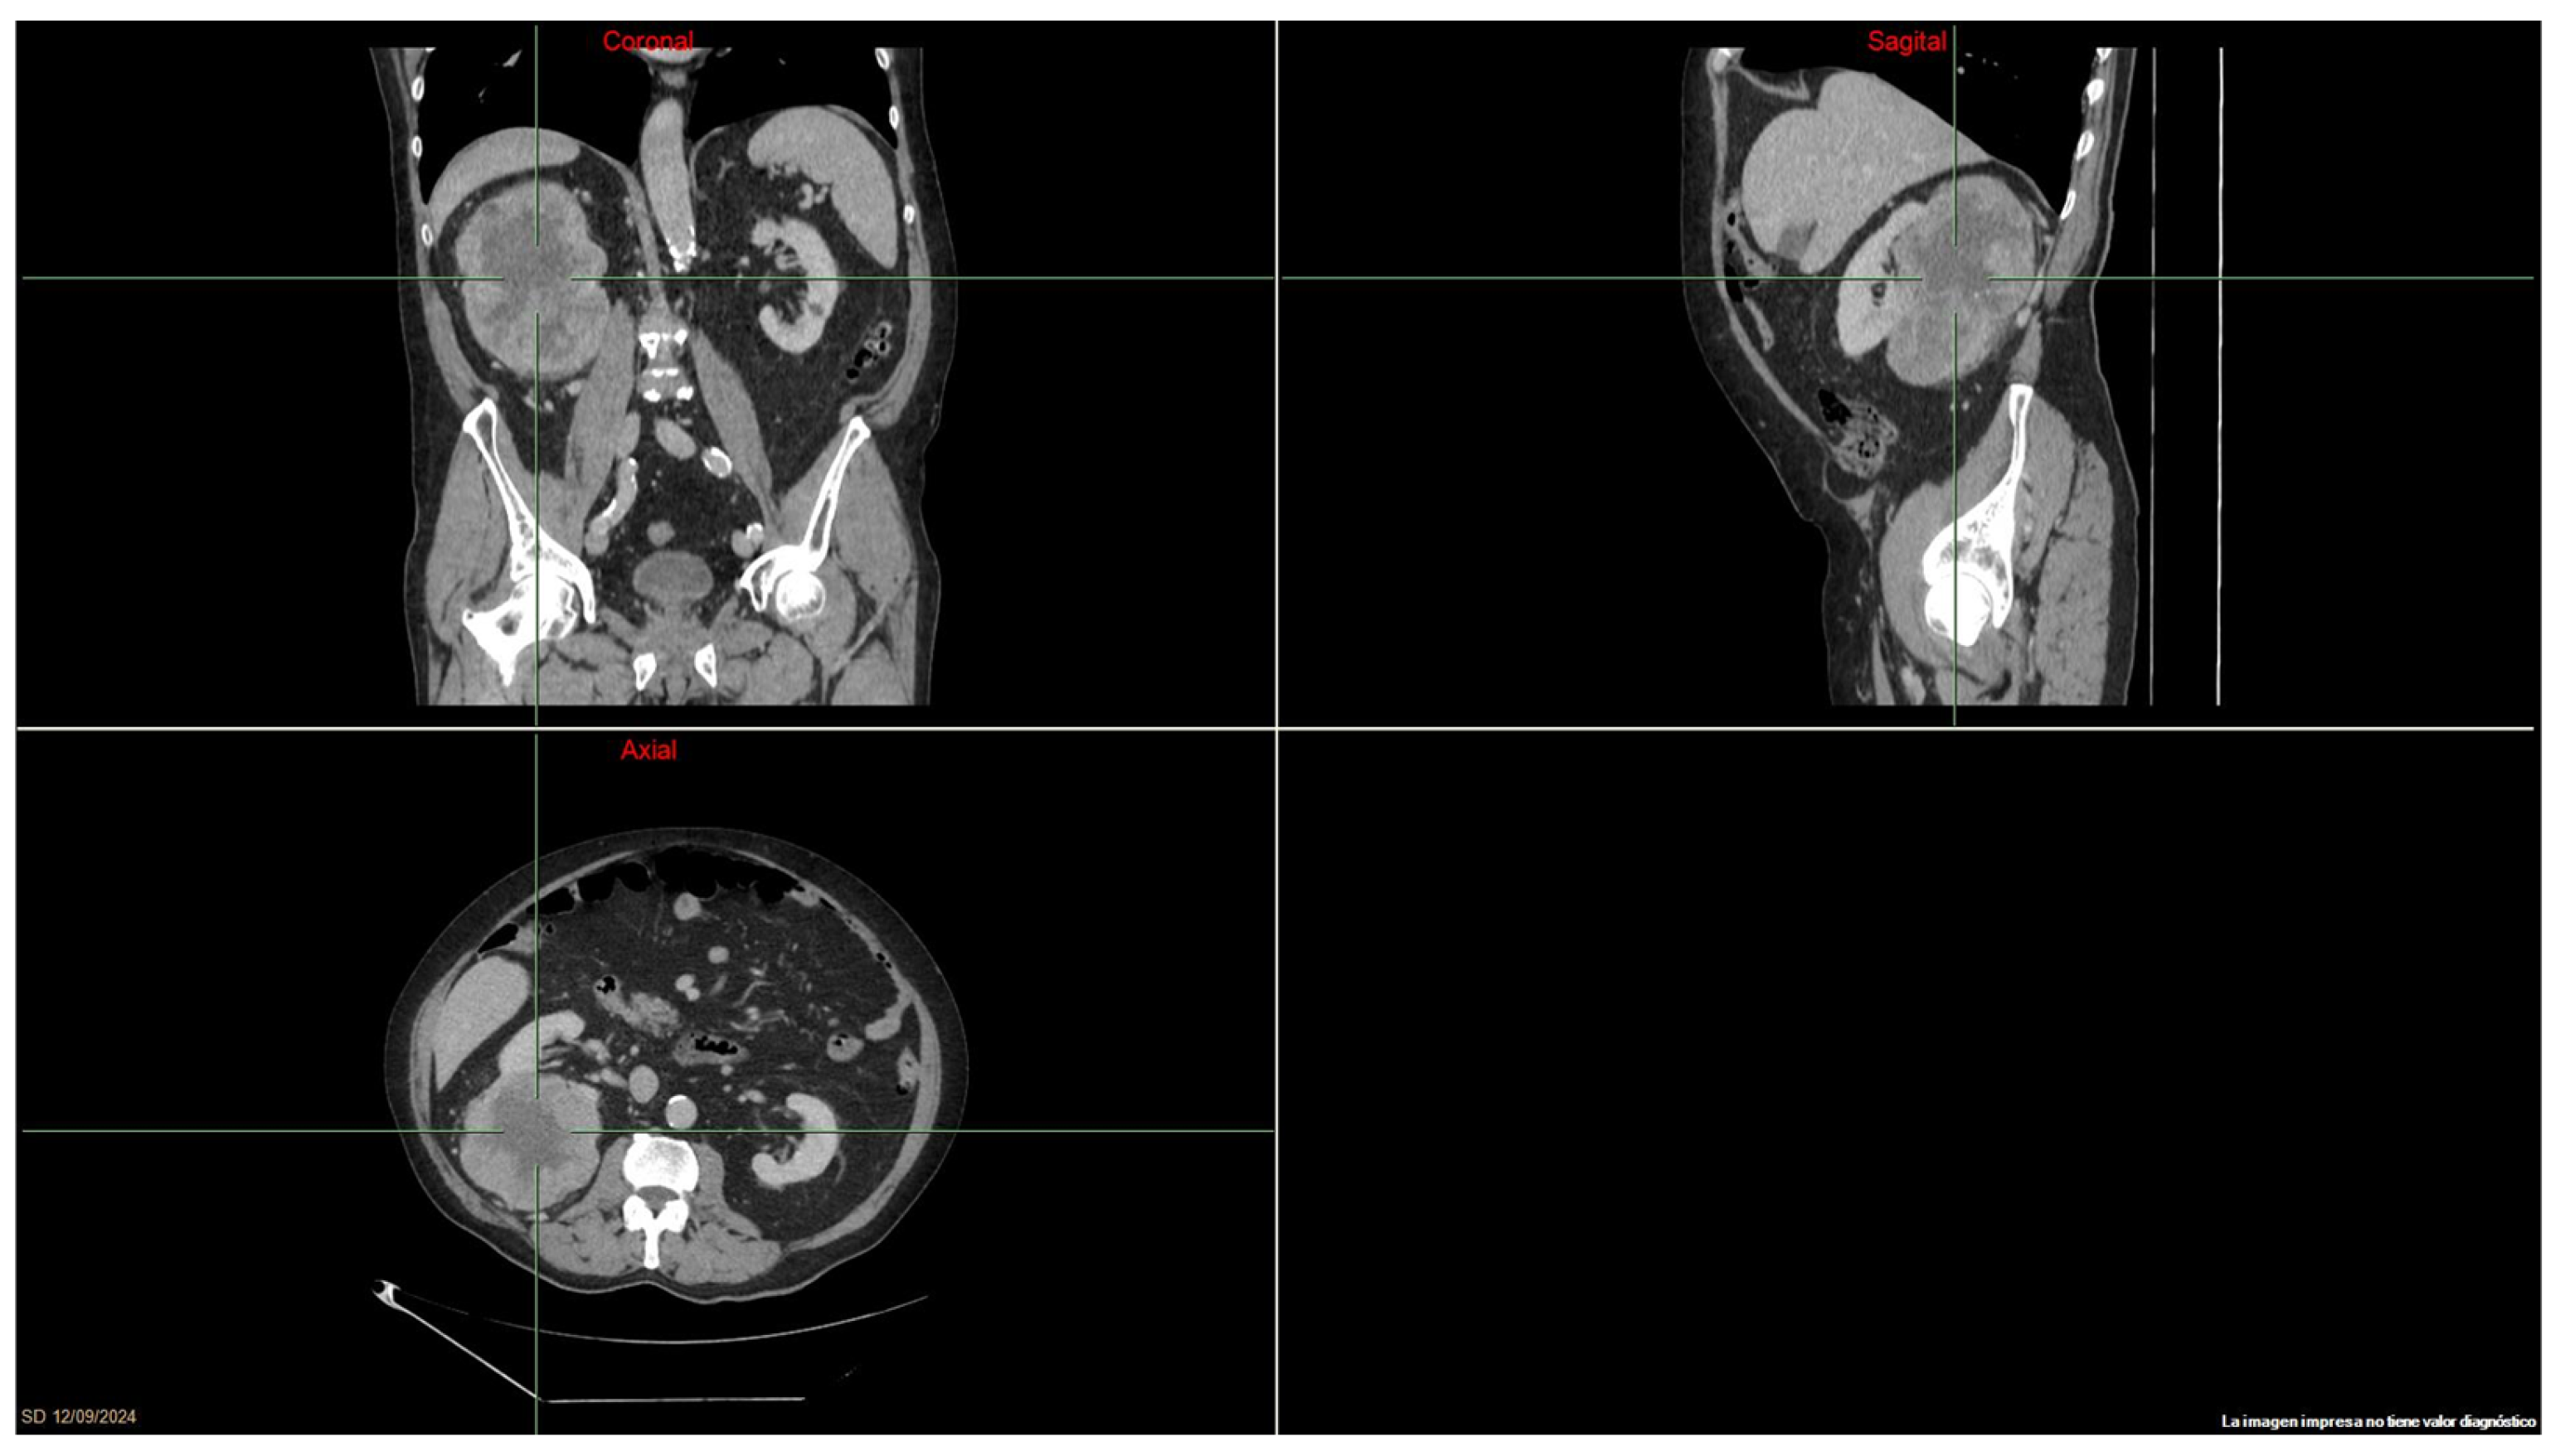

Case Presentations: In June 2023, a 33-year-old woman affected by Hereditary Leiomyomatosis and renal-cell cancer (HLRCC) started first-line therapy with nivolumab and cabozantinib for mediastinal and abdominal lymph node recurrence (short axis of 29, 21, and 21 mm) of a previously radically resected FH-d RCC. After one year of treatment, almost all the lymphadenopathies achieved a radiologic partial response, which was then consolidated with radiotherapy. Four months later, the most recent CT scan showed complete response, and the treatment is still ongoing.

A second case of FHd-RCC in a young male patient came to the attention of our department in July 2023. Following radical nephrectomy, a post-operative CT scan showed the presence of two pathological abdominal lymph nodes (short axis of 11 mm). Hence, the patient started first-line nivolumab–cabozantinib. Radiotherapy was performed as a consolidative treatment six months after the start of systemic therapy, with a CT scan showing a radiologically complete response. Fourteen months from the start of treatment, the patient still has no evidence of disease and continues nivolumab–cabozantinib therapy.